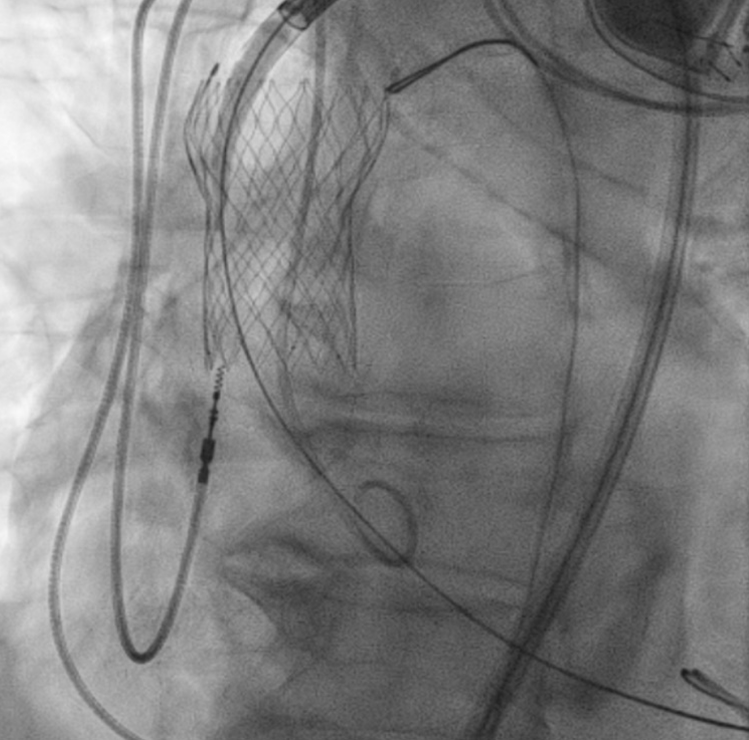

瓣膜释放:通过快速心室起搏降低心输出量,减少瓣膜移位风险,随后启动球囊扩张,将Sapien瓣膜精准释放于目标位置。释放后即刻造影与TEE显示:瓣膜定位良好,无明显移位,瓣叶活动正常。

Successful deployment of Sapien valve

Sapien 瓣膜成功释放

患者术中未出现严重血流动力学波动,无脑血管事件、大出血、血管并发症等不良事件。

术后第1天复查超声心动图:Sapien瓣膜位置固定良好,平均主动脉瓣跨瓣压差降至12mmHg(较术前43mmHg显著改善),无主动脉瓣反流;移位的Evolut FX瓣膜仍固定于主动脉升部,未对血流产生明显影响,也未出现瓣膜血栓形成迹象。